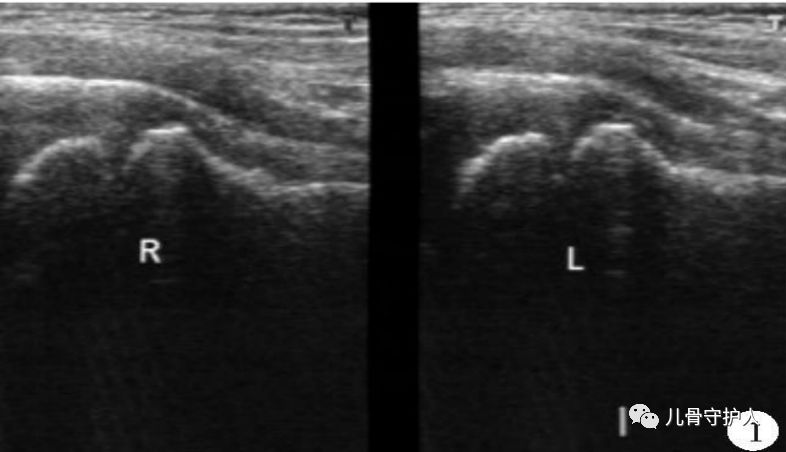

4.X:骨盆轻度倾斜,髋关节囊肿胀,关节间隙增宽,无骨质破坏。B超:患髋股骨颈颈前间隙增宽,双侧差值大于1mm。滑膜增厚,关节积液。